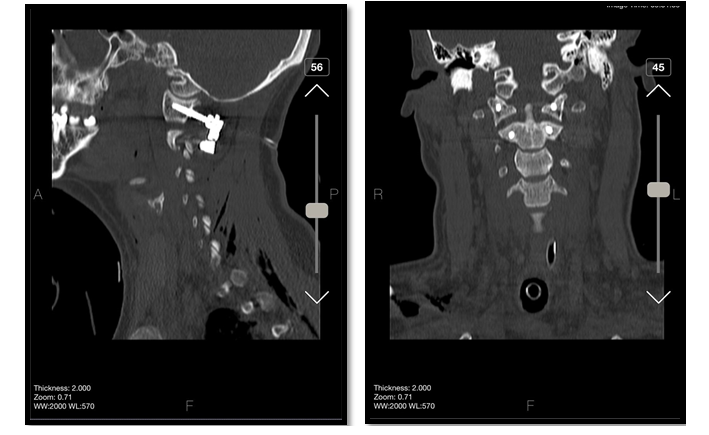

Under general anesthesia, the patient was placed in the supine position. Under fluoroscopy guide and C-ARM imaging monitoring, several times of closed reductions were attempted through gradual manual cranial traction from flexion to extension (Figure-2). To sum up the surgery process; we can say that three phases were done, first of all, the flexion of the head and neck with traction was done, then neutral position applied when the odontoid process was near the posterior wall of the anterior C1 arch. During the process, the odontoid process was locked in the inferior of the anterior C1 arch. Therefore, in the 3rd phase, we decided to push back the odontoid process by using an impactor (Figure-3) through the retro pharynx. The maneuver was successful, and the odontoid was placed in its position. All phases were done under neuromonitoring. Then, He was positioned from supine to prone to fix the C1 and C2 vertebrae. We exposed the axis and atlas surgically via a posterior approach. The attempts to relocate the normal axis-atlas alignment to fuse the facet joints failed. The lateral mass screw was applied for C1, and pedicular 24*8 mm in the right part of C2 and 26*8 mm in the left one was used. The fusion was applied to reduce the ligament injuries (Figure-4 and 5).

Figure 4. intraoperative fluoroscopic images

Figure 5. post-operative CT images show Lateral mass screw was applied for C1, and a pedicular measuring 24*8 mm in the right part of C2 and 26*4 mm in the left one were used. The fusion was applied to reduce ligament injuries